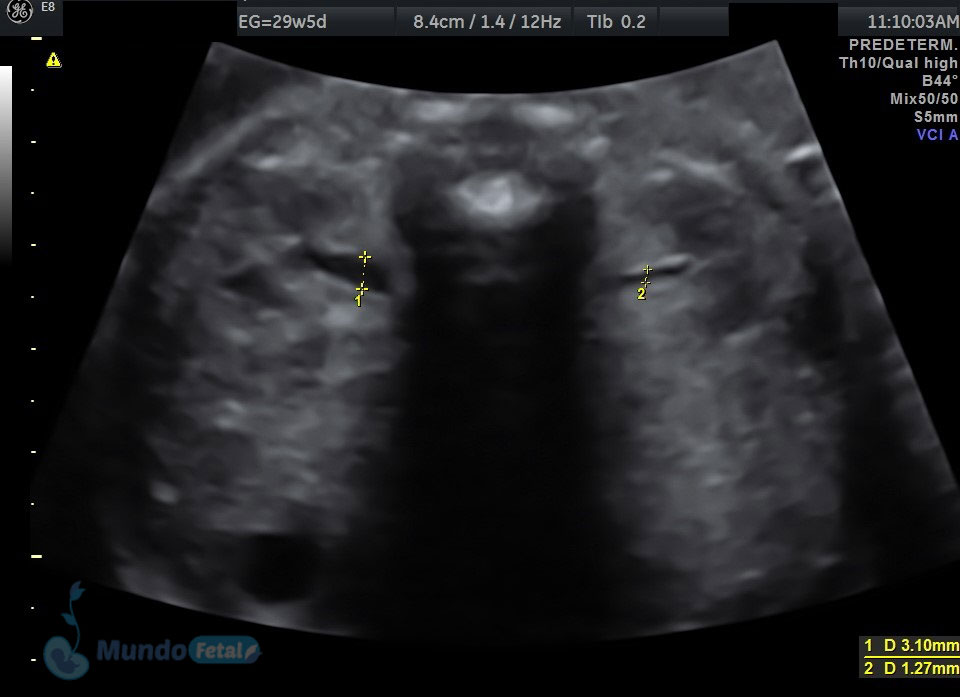

ANATOMICO-ORBITAS